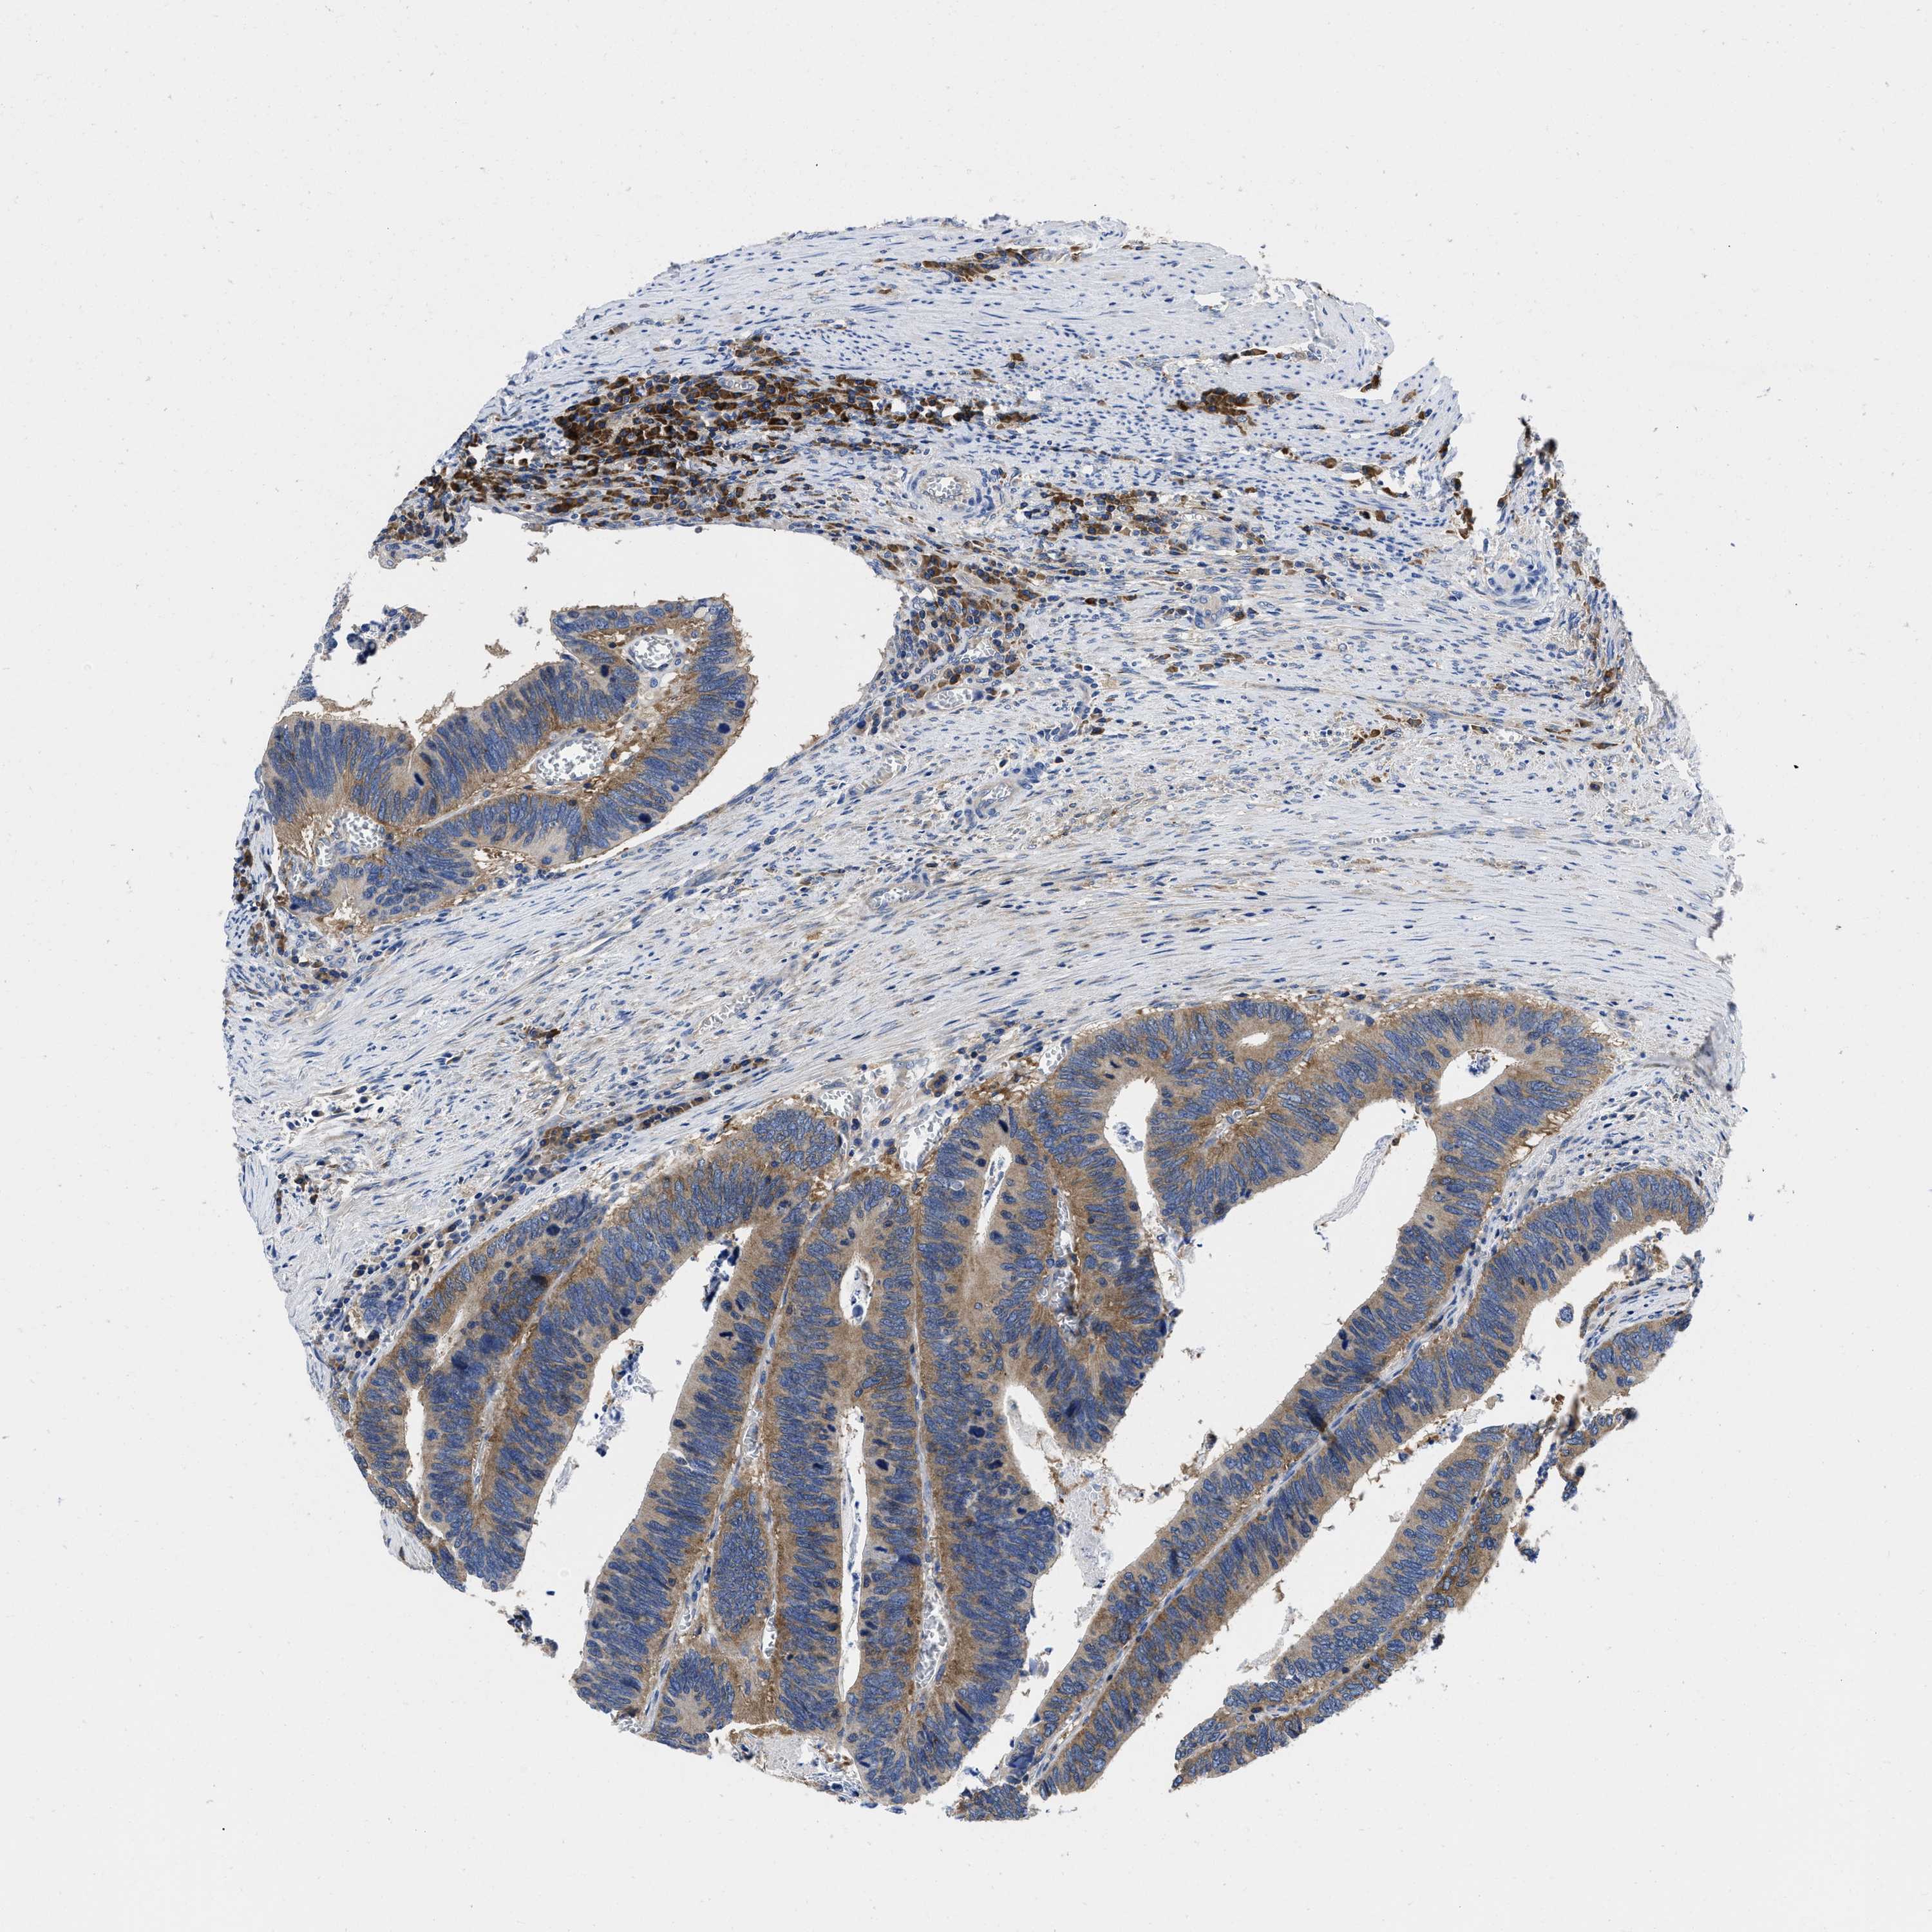

CANCER COLORECTAL CANCER Show tissue menu

Colorectal cancer

Human cancer

Colon adenocarcinoma

Rectum adenocarcinoma